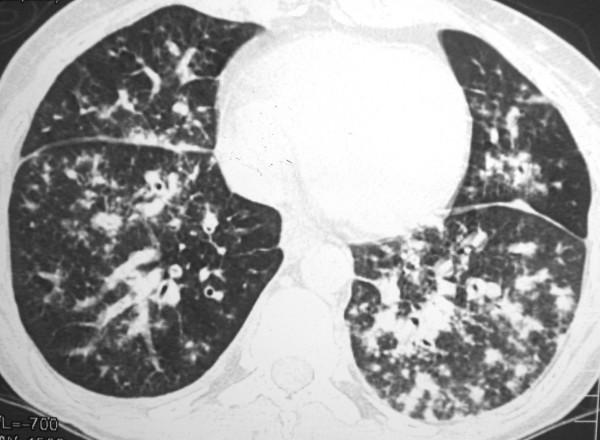

Approximately 90% to 95% of Kaposi sarcoma cases occur in human immunodeficiency virus - infected homosexual and bisexual men. Pulmonary Kaposi sarcoma is uncommon in women, and rarely considered as a potential cause of diffuse lung disease in women with acquired immunodeficiency syndrome. The disease is usually mistaken clinically for pulmonary infection. A 32-year-old woman was admitted with a 2-month history of dyspnea, evening fever, hemoptysis, weight loss, and generalized adenomegaly. Physical examination showed erythematous macules in the lower limbs. Skin and open lung biopsy demonstrated Kaposi sarcoma. Computerized tomography demonstrated peribronchovascular interstitial thickening. Although uncommon, pulmonary Kaposi sarcoma should be considered in the differential diagnosis of diffuse lung disease in women with AIDS.

约90%至95%的卡波西肉瘤病例发生于感染人类免疫缺陷病毒的同性恋和双性恋男性。肺卡波西肉瘤在女性中并不常见,在获得性免疫缺陷综合征女性患者中很少被视为弥漫性肺病的潜在病因。临床上该病通常被误诊为肺部感染。一名32岁女性因2个月的呼吸困难、午后发热、咯血、体重减轻及全身淋巴结肿大入院。体格检查发现下肢有红斑。皮肤及开放性肺活检显示为卡波西肉瘤。计算机断层扫描显示支气管血管周围间质增厚。尽管罕见,但在艾滋病女性患者弥漫性肺病的鉴别诊断中应考虑肺卡波西肉瘤。